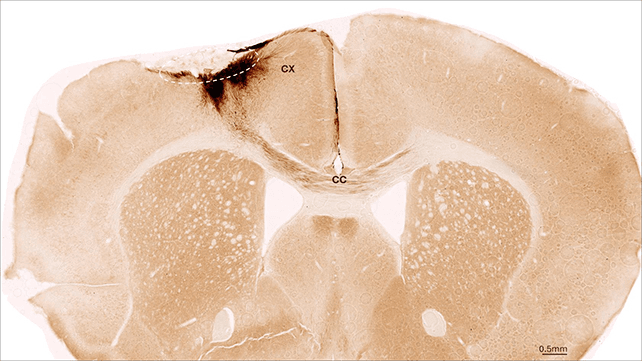

Utilizando ratones con daño cerebral inducido por un accidente cerebrovascular, los investigadores descubrieron que las inyecciones de células madre humanas podían convertirse con éxito en células cerebrales inmaduras. Los resultados fueron espectaculares: la mayoría de las células implantadas permanecieron en su lugar, desarrollando características de neuronas plenamente funcionales y comunicándose con las células circundantes.

Además, los investigadores observaron la autorreparación de los vasos sanguíneos, la reducción de la inflamación cerebral y el fortalecimiento de la barrera hematoencefálica. Los ratones incluso mostraron signos de mejora en el movimiento y la coordinación, un hallazgo clave, ya que los accidentes cerebrovasculares pueden afectar gravemente el control motor del cuerpo.